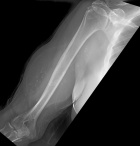

G.O. - 75 year old male with a right upper arm mass for 25 years; the mass never bothered him until a few months ago when he began having intermittent discomfort, he does not think the mass has grown recently